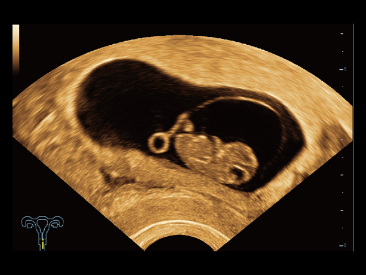

Selain kualitas gambar premium, Resona 7 juga meningkatkan kemampuan penelitian klinis dengan V Flow revolusioner untuk evaluasi hemodinamika vaskular, serta pengambilan penampang tercanggih dari rangkaian data 3D untuk diagnosis CNS pada janin. Kombinasi pengoperasian multisentuh berbasis gerakan yang paling intuitif dengan semua fitur klinis penting membuat Resona 7 menjadi gebrakan baru dalam inovasi ultrasound.